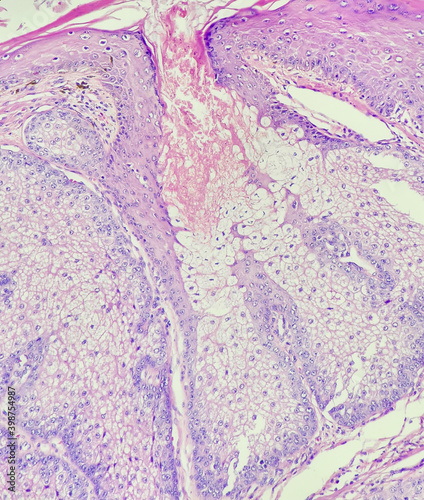

Mikrofotografi - Plakater, Poster, Billeder på lærred